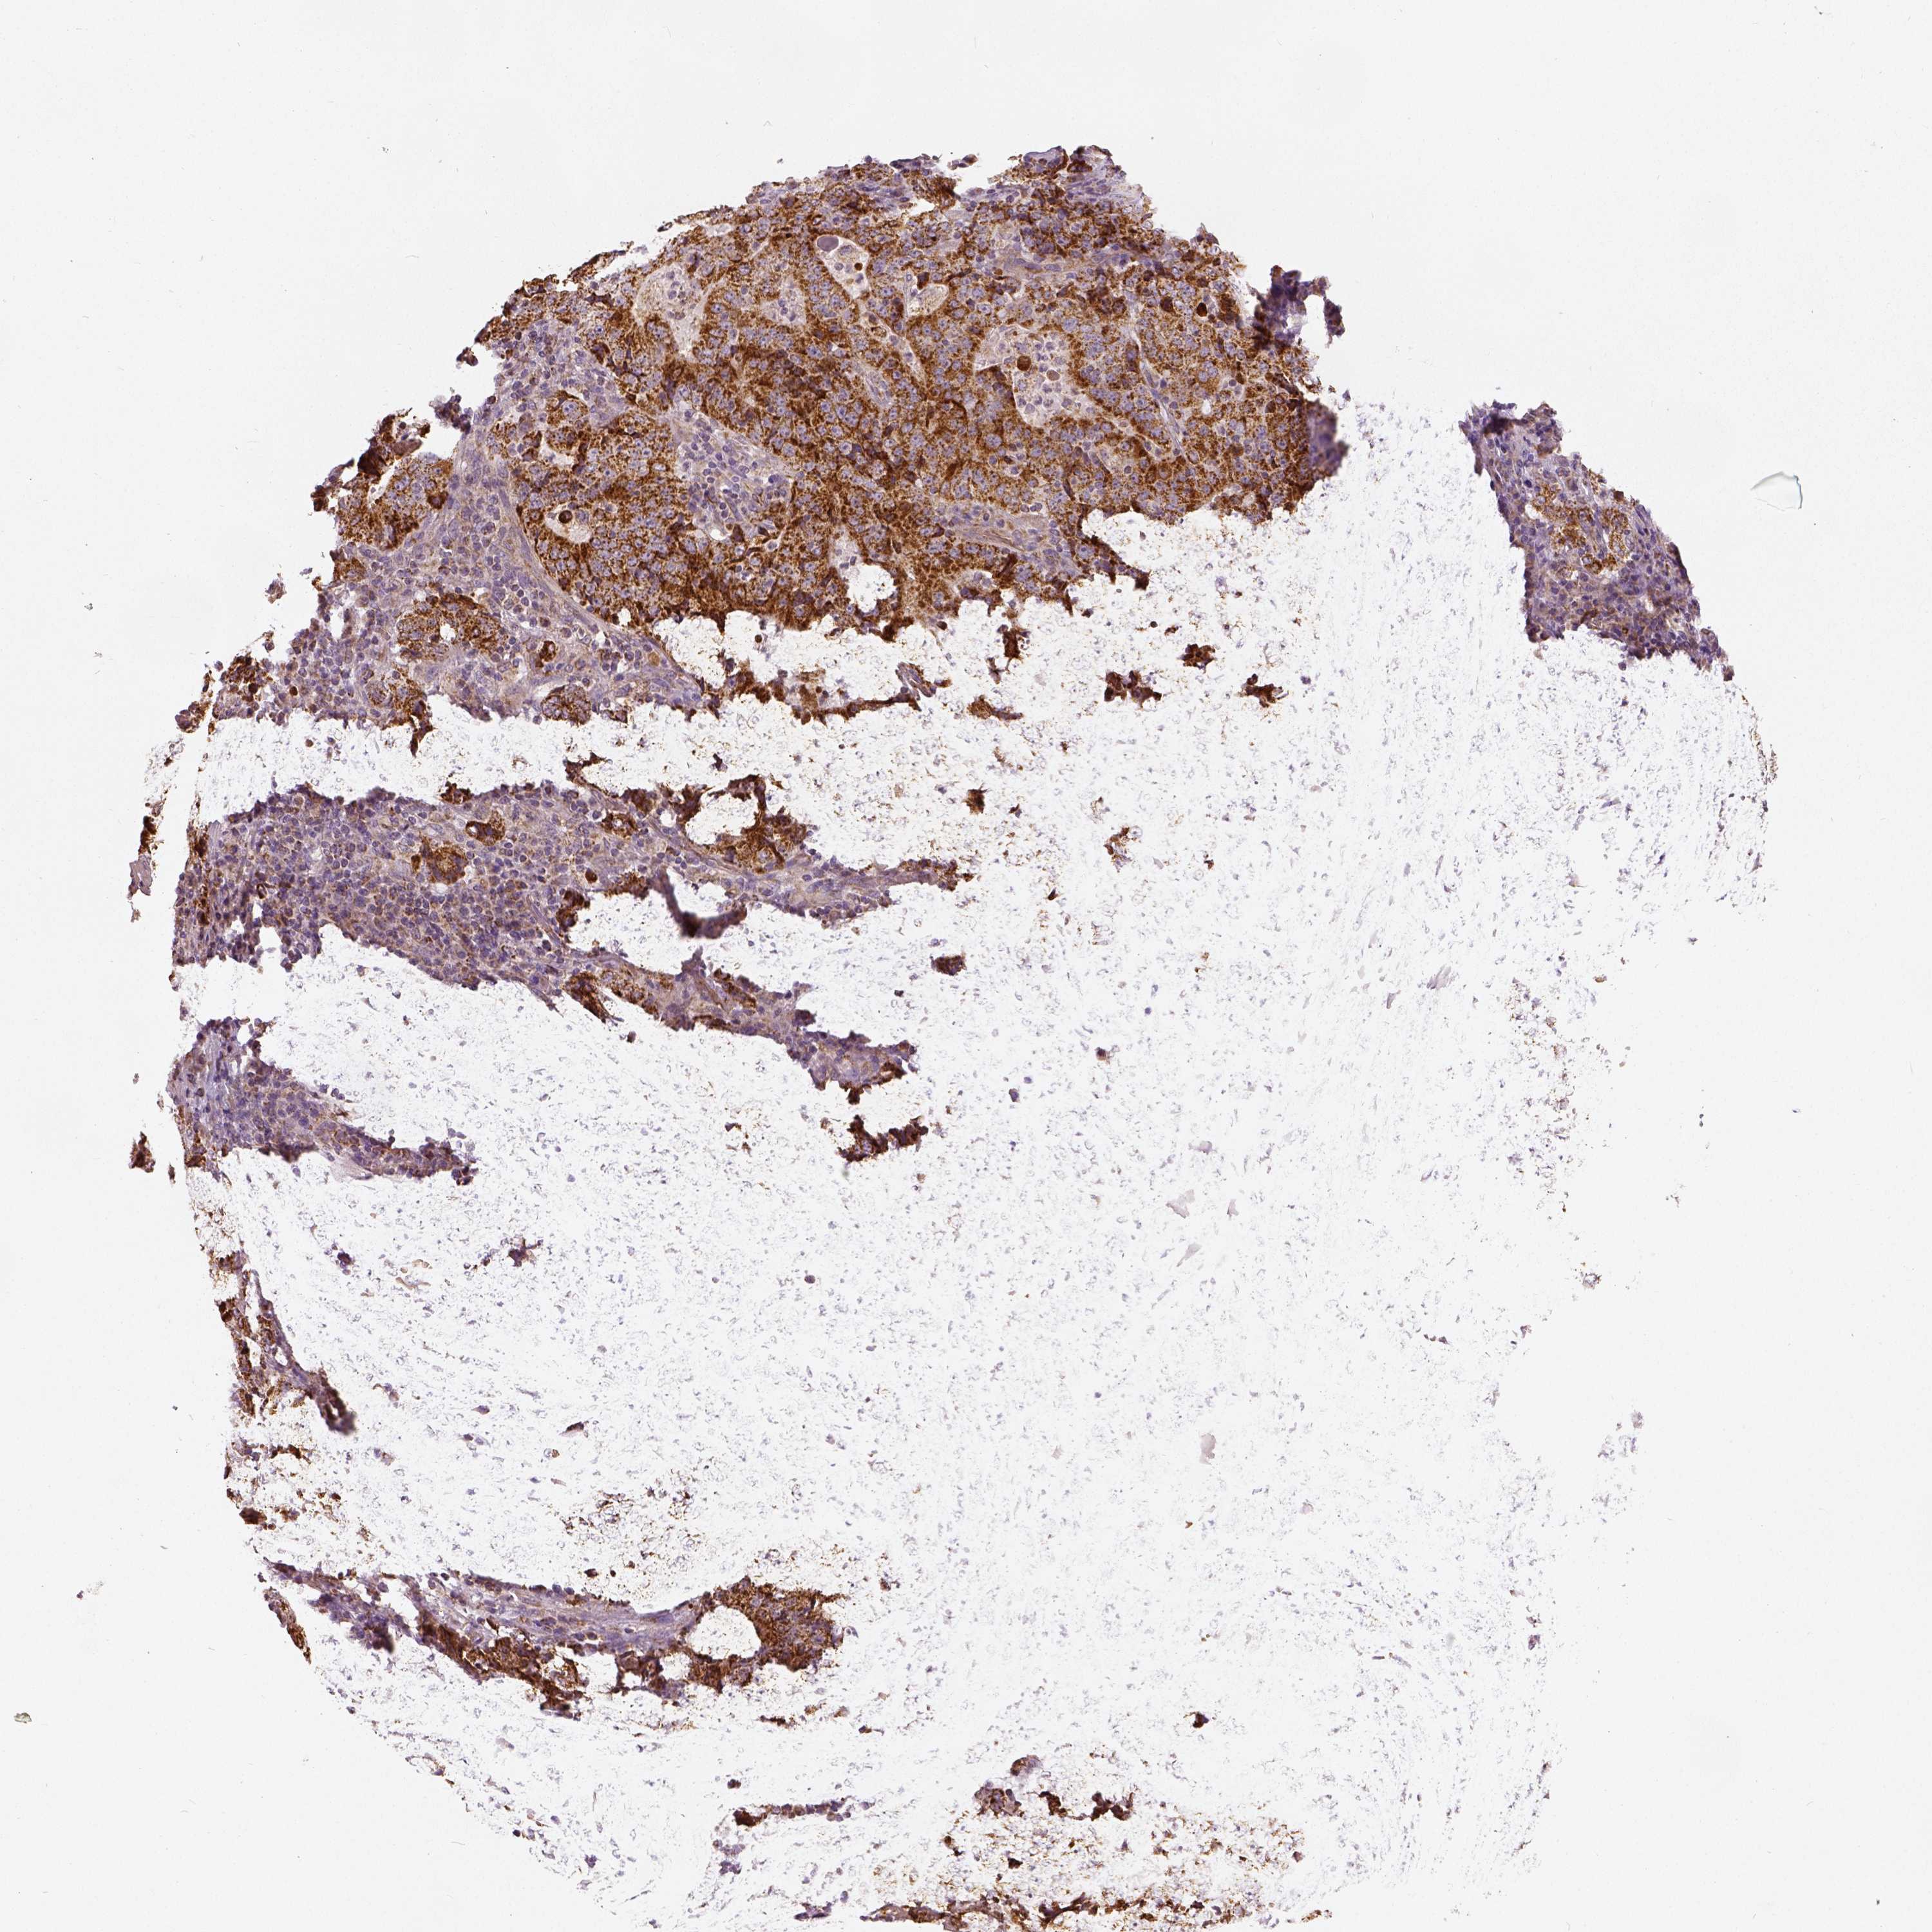

STOMACH CANCER - Protein expressioni

A mouse-over function shows sample information and annotation data. Click on an image to view it in a full screen mode. Samples can be filtered based on level of antibody staining by selecting one or several of the following categories: high, medium, low and not detected. The assay and annotation is described here.

Note that samples used for immunohistochemistry by the Human Protein Atlas do not correspond to samples in the TCGA dataset.

Antibody stainingi

Antibody staining in the annotated cell types in the current human tissue is reported as not detected, low, medium, or high, based on conventional immunohistochemistry profiling in selected tissues. This score is based on the combination of the staining intensity and fraction of stained cells.

Each image is clickable and will lead to virtual microscopy that enables deeper exploration of all samples and also displays staining intensity scores, fraction scores and subcellular localization as well as patient and tissue information for each sample.

Antibody HPA036978

Antibody HPA036979

Antibody CAB068215

Staining

High

Medium

Low

Not detected

Intensity

Strong

Moderate

Weak

Negative

Quantity

>75%

75%-25%

<25%

None

Location

Nuclear

Cytoplasmic/membranous

Cytoplasmic/membranous,nuclear

Adenocarcinoma, NOS